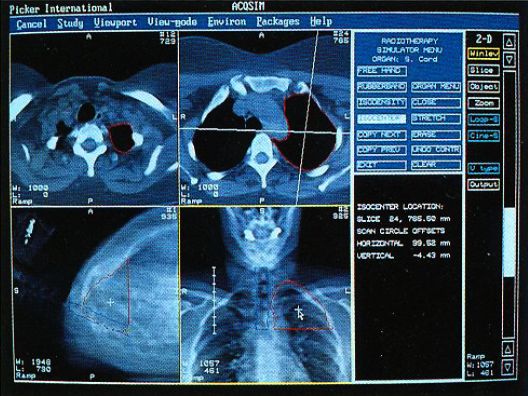

Picker International (Cleveland, Ohio) was one of the major manufacturers of medical imaging equipment, having started as an X-ray machine company in 1909. They expanded to high tech imaging modalities including Computed Tomography (CT or CAT), Magnetic Resonance Imaging (MRI), Positron Emission Tomography (PET), ultrasound, and others, while still providing basic (but modern) X-ray equipment. In the early 1990s Picker needed a platform for a radiation treatment planning system that was being developed to go along with their high-end CT scanners. They became interested in the DDD technology to provide a competitive advantage and gave us some additional funding (while still DDD) to support the effort. Now with Picker, everything had to have a "Q" in the name - standing for quality or something. So after some repackaging and design enhancements including optimization for ray tracing, what would probably have been called Voxelscope III (VS3) became the VoxelQ (or simply "VQ") to be incorporated into the AcQSim or AcQPlan treatment planning system, and to be bundled with high-end CT scanners, among others.

Here are typical examples of VoxelQ displays. These are mostly only windows, not the full screen which is more along the lines of the last block of AcQSim photos.

VoxelQ Multiplanar Reformatting (Axial, Saggital, Coronal, Curved)

AcQSim Screen Examples